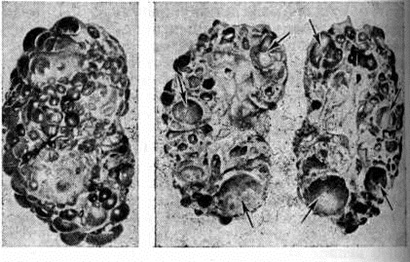

КистаКиста (греческий kystis пузырь) — патологическая полость в тканях или органах, имеющая стенку и содержимое. От термина «киста» происходят прилагательные «кистовидный», «кистозный», употребляемые в тех случаях, когда то или другое патологический изменение сопровождается образованием Киста. Размер Киста, содержимое и строение стенки бывают различными в зависимости от механизма и давности образования, локализации и так далее. Различают истинные Киста и ложные (псевдокисты): истинные выстланы эпителием или реже эндотелием, ложные специальной выстилки не имеют. Киста бывают приобретёнными и врождёнными, то есть возникающими при порочном формировании тканей и органов. По механизму образования различают Киста ретенционные, рамолиционные, паразитарные, травматические, дизонтогенетические, опухолевые. Ретенционные кисты, как правило, приобретённые, встречаются в различных желёз исто-секреторных органах и являются следствием затруднения или полного прекращения оттока секрета из железы вследствие закупорки протока конкрементом, пробкой из сгустившегося секрета, сдавлением протока опухолью или рубцом. Секрет, накапливаясь в протоке или в железистой дольке, растягивает их, образуя постепенно увеличивающуюся полость с сальным, слизистым, водянистым и другим содержимым. Таковы Киста сальных, слюнных, молочных желёз, фолликулярные Киста яичников, поджелудочной, предстательной желёз и другие Стенка ретенционной Киста выстлана уплощённым эпителием железы или её протока. При внутриутробных атрезиях протоков желёз развиваются врождённые ретенционные Киста Рамолиционные кисты (Киста от размягчения) образуются в компактной ткани при очаговом омертвении её (при кровоизлиянии, воспалении, некрозе, инфаркте) и последующем размягчении, разжижении и резорбции мёртвого субстрата. Стенка такой Киста образована тканью того органа, в котором она локализуется, но в дальнейшем может заместиться соединительной тканью, а в мозге глиозной. Рамолиционные Киста обнаруживают в головном, редко в спинном мозге, в опухолях (например, глиоме, фиброме). К рамолиционным относятся Киста жёлтого тела яичников, корневые внутрипульпарные зубные Киста (смотри полный свод знаний Зубная киста), костные Киста при остеобластокластомах, фиброзном остите. Паразитарные кисты представляют собой пузырную личиночную стадию (финны) ленточных червей. К ним относятся эхинококковая Киста, или эхинококк (смотри полный свод знаний Эхинококков), и цистицерк (смотри полный свод знаний Цистицеркоз). Травматические кисты возникают в результате прижизненного смещения эпителиальных тканей. К ним относятся травматические эпителиальные Киста пальцев и ладоней вследствие внедрения эпителиального покрова в подлежащую ткань и последующего накопления секрета в образовавшемся эпителиальном мешочке. Аналогичного происхождения травматические эпителиальные Киста радужной оболочки глаза, а также травматические Киста поджелудочной железы. Считают, что некоторые костные Киста также травматического происхождения. Дизонтогенетические кисты чаще всего врождённые; они представляют собой кистовидное превращение иногда сохраняющихся эмбриональных каналов и щелей. В других случаях Киста возникают в смещённых при формировании эмбриона тканях, чаще в желёз истых. К дизонтогенетическим относят бранхиогенные кисты (смотри полный свод знаний) из сохранившихся жаберных щелей, Киста из остатков желточно-кишечного хода (энтерокистомы); Киста предстательной желёз ы возникают в связи с нарушением формирования парамезонефротических протоков или заращением выходного отверстия vesiculae prostaticae. К возникшим как порок развития относятся сирингоцистаденомы и сирингоэпителиомы — порок развития потовых желёз , пар овариальные кисты (смотри полный свод знаний), эндометриальные Киста яичников (так называемый шоколадные), дермоидные Киста, множественные кисты почек, печени (рисунок 1 и 2), бронхов и другие. Иногда вследствие нарушения развития организма отмечается одновременное образование врождённых Киста поджелудочной желёз ы, печени, почек, лёгких, яичников и центральной нервной системы Опухолевые кисты возникают в тех случаях, когда растущая ткань опухоли формирует однокамерные, чаще многокамерные полости (например, многокамерная краниофарингиома). |

Рис. 1. | ||

Рис. 2. | ||